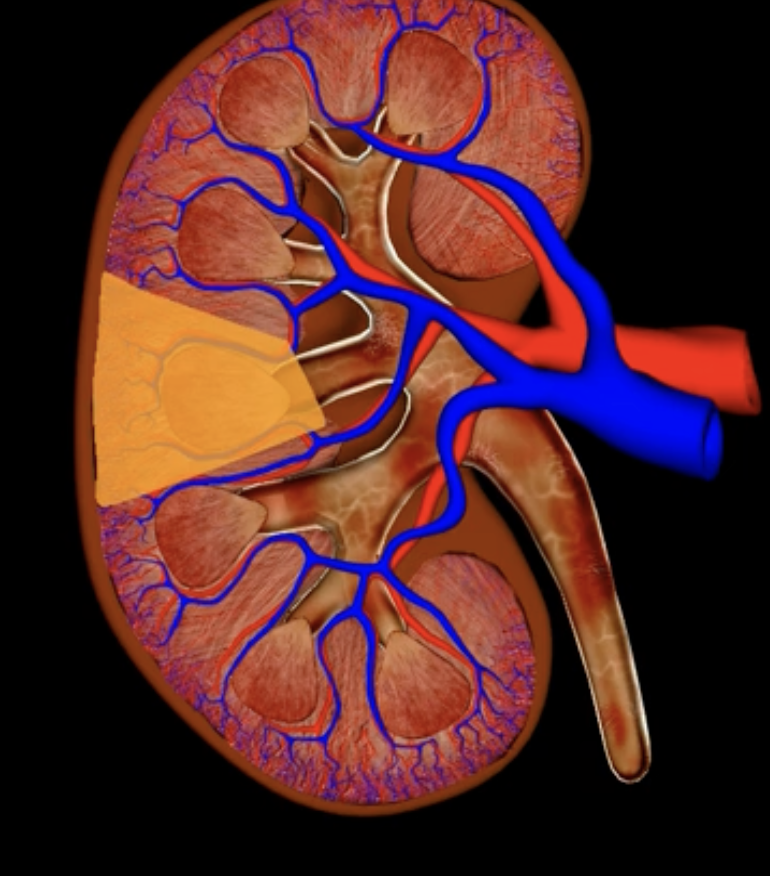

renal lobe

orange